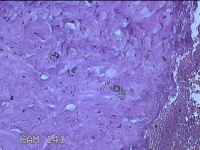

性别

女

年龄

27岁

临床诊断

乳腺脓肿

一般病史

发现右侧乳腺脓肿1个月余,伴局部疼痛不适。

标本名称

右侧乳头下方结节

大体所见

灰白暗红色结节0.8x0.5x0.3cm一个,表面糜烂。

图1

组织没固定好